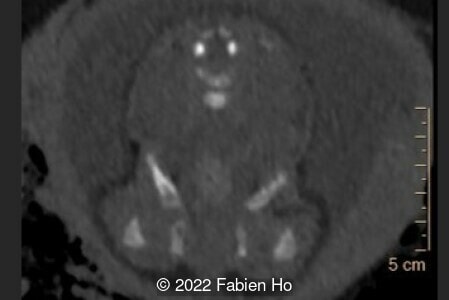

A CT scan was subsequently performed at 32 weeks gestation

The prenatal CT scan showed:

- Low bone density of skull and lower limbs

- Normal pelvis without iliac spine or other anomaly

- Very short long bones with curved femurs, tibias and fibulas. The curvature of the long bones reaches a 90° angle concerning for fracture. Upper limbs are moderately curved without fracture.